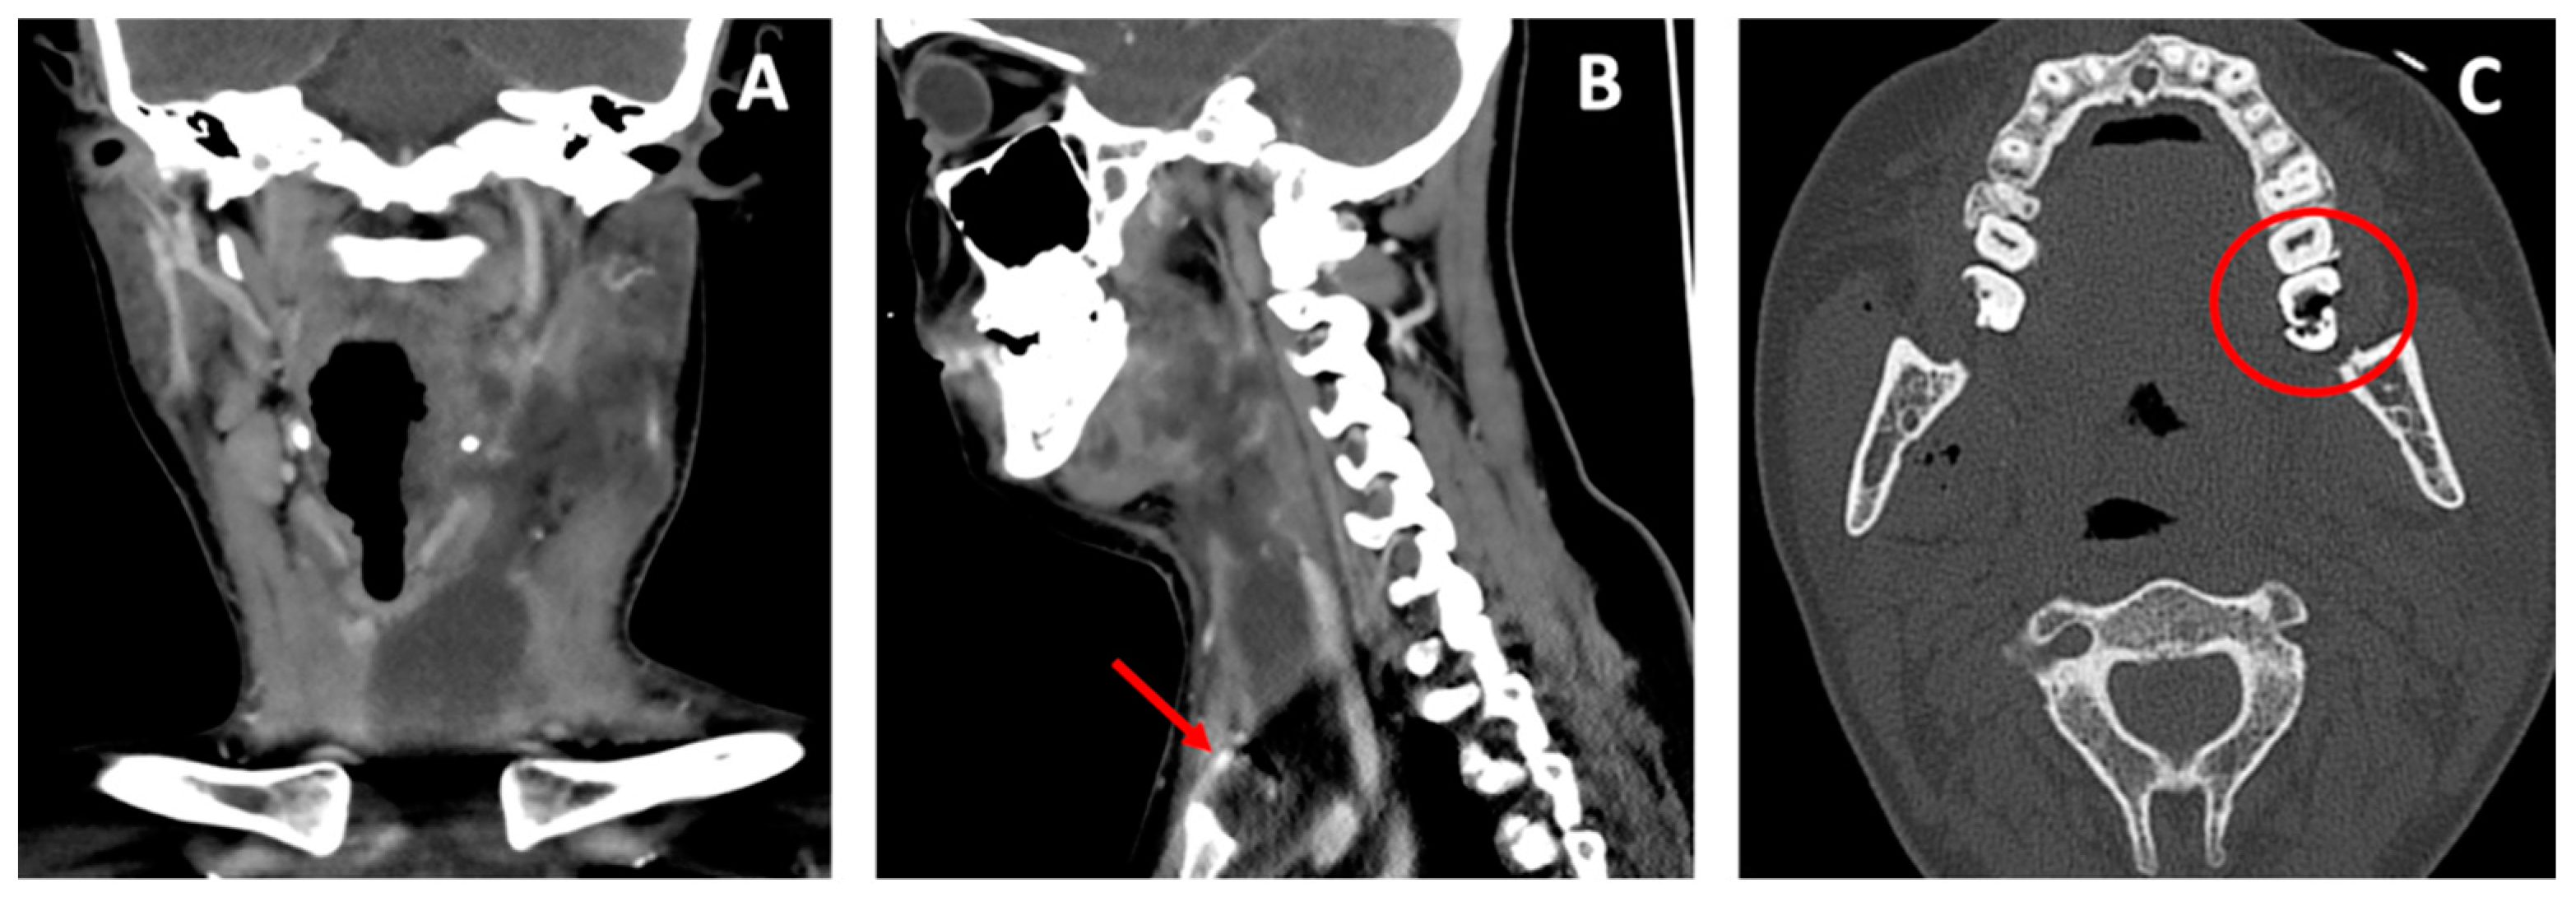

Herein, we present the case of a 28-year-old woman admitted to our emergency department presenting with left submandibular swelling that had arisen five days earlier, and was associated with a fever, progressive dysphagia, trismus and dyspnea. The ENT examination revealed a painful left submandibular swelling covered with hyperemic and warm skin. The endoscopy of the upper airway tract showed swelling on the left side of the oropharynx and hypopharynx, and a mobility impairment of the left vocal fold. The head–neck computed tomography (CT) scan performed with and without a contrast agent showed a voluminous mass involving the left submandibular region, perimandibular soft tissues, masseter muscle, tonsillar region and the parapharyngeal space, resulting in the aerial column deviating to the right. The swelling caused the compression of the internal jugular vein and extended up to the anterior mediastinum, behind the sternal manubrium (Figure 1A,B).

Figure 1.

Computed tomography scan of the abscess affecting the deep space of the neck and the anterior mediastinum in coronal view (A). The red arrow in sagittal view shows the abscess behind the sternal manubrium (B). In the axial view the red circle shows the broken third inferior left molar (C).

The CT showed that the probable origin of the abscess was an odontogenic infection coming from the inferior left molars (Figure 1C).